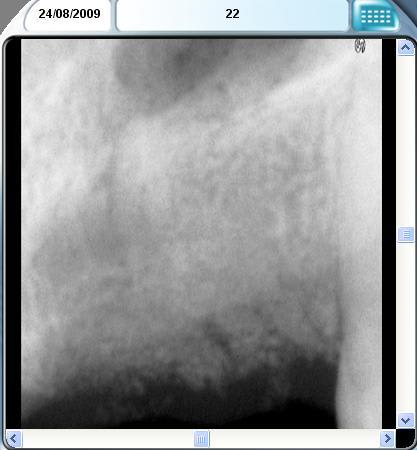

CF cas similaire antérieur avec un vrai gruyère osseux......la patiente veut aussi différer les implants pour raisons financières.

12 bilan tbr0kg - Eugenol

12 postop m665pp - Eugenol

22 bilan bew07m - Eugenol

22 postop j7az46 - Eugenol

Simp bilan ejqvaq - Eugenol

2009 08 04 rumszi - Eugenol

Simp postop iq5cd8 - Eugenol